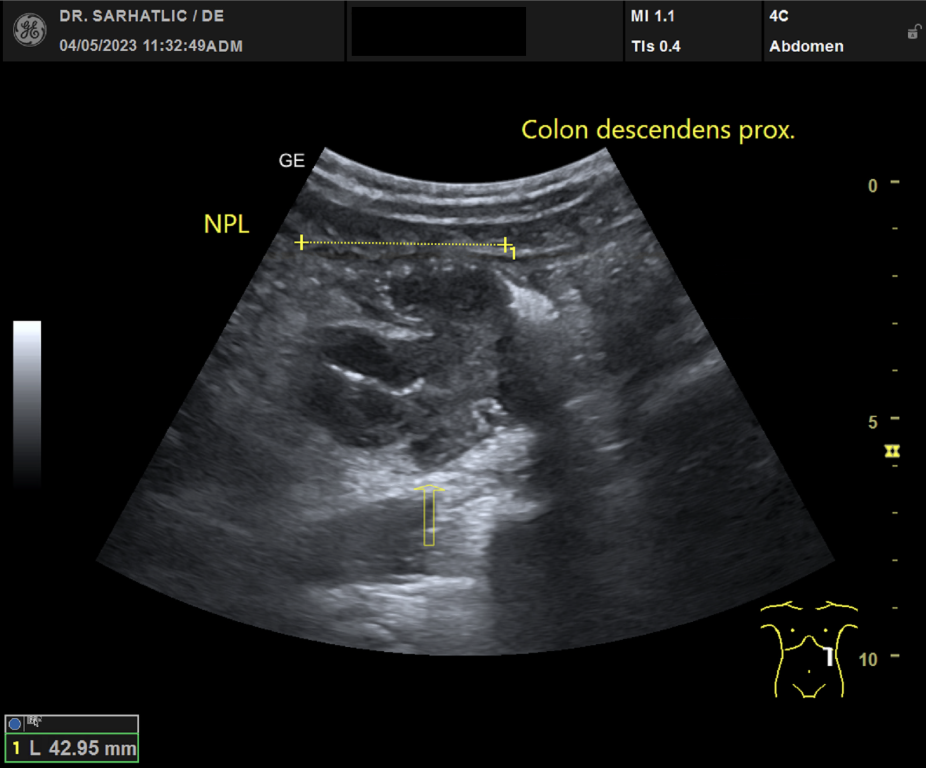

MODERNE ULTRASCHALLDIAGNOSTIK- Modernes Farbdoppler-Ultraschallgerät

- Hochauflösende Schallköpfe

- Detaillierte Organuntersuchungen

- Ultraschall aller inneren Organe (z. B. Leber, Bauchspeicheldrüse, Nieren, Prostata, Schilddrüse)

- Krebsvorsorge im internistischen Spektrum